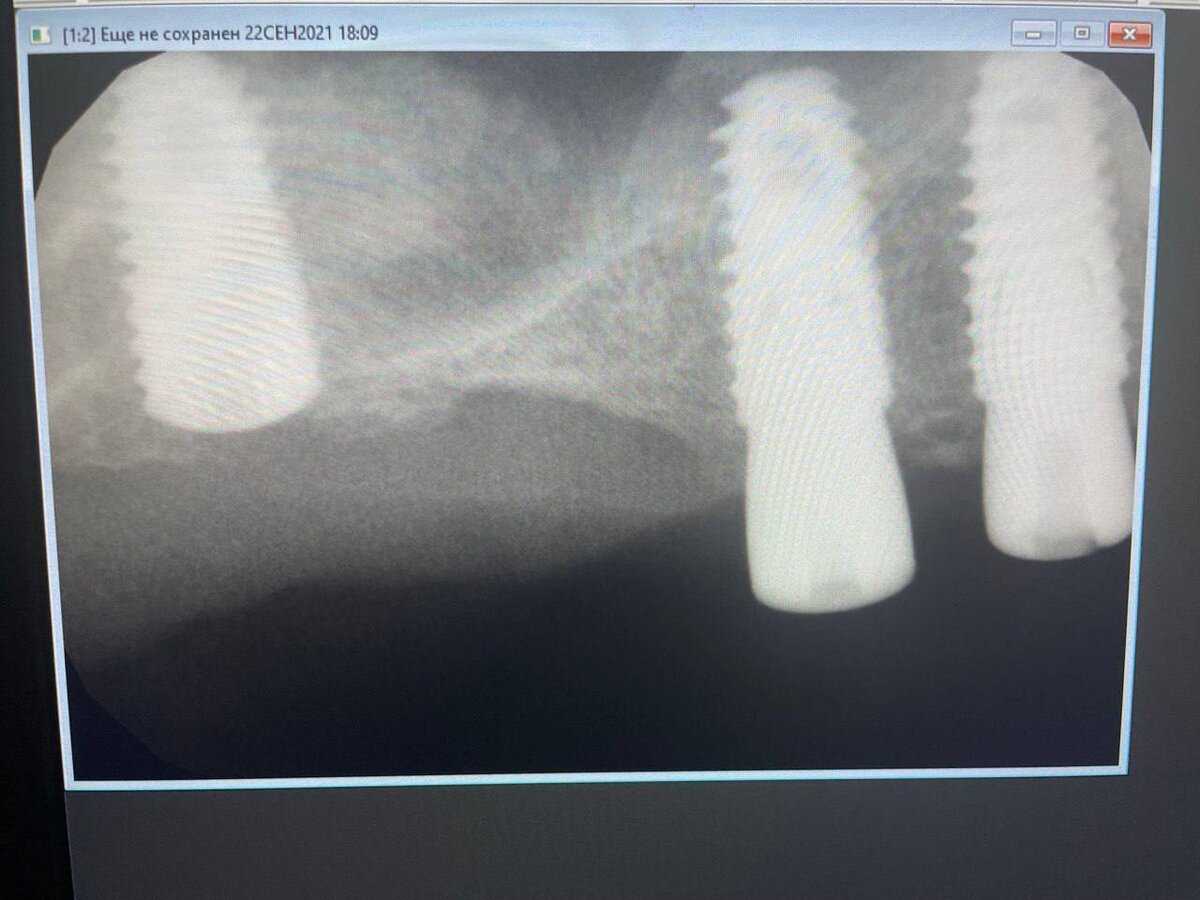

В данном случае на два имплантата мы установили формирователи, а на третий нет. И первое, что спросила пациентка на осмотре: «А вы мне точно три имплантата установили? Я смотрела, и муж смотрел, и мы увидели только два». Пришлось показывать рентген и объяснять, что их там действительно три!